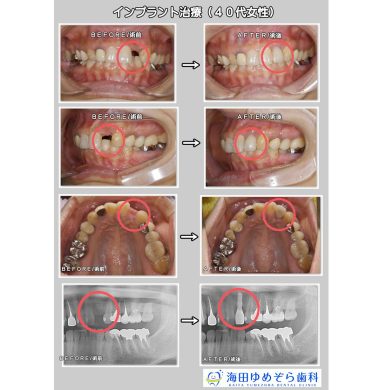

インプラントの症例 GBR法/骨補填材使用

☆治療内容

インプラント

☆治療期間

9ヶ月

☆治療費用

495,000円(税込)

☆リスク

術後の出血、腫れ、痛みの可能性があります